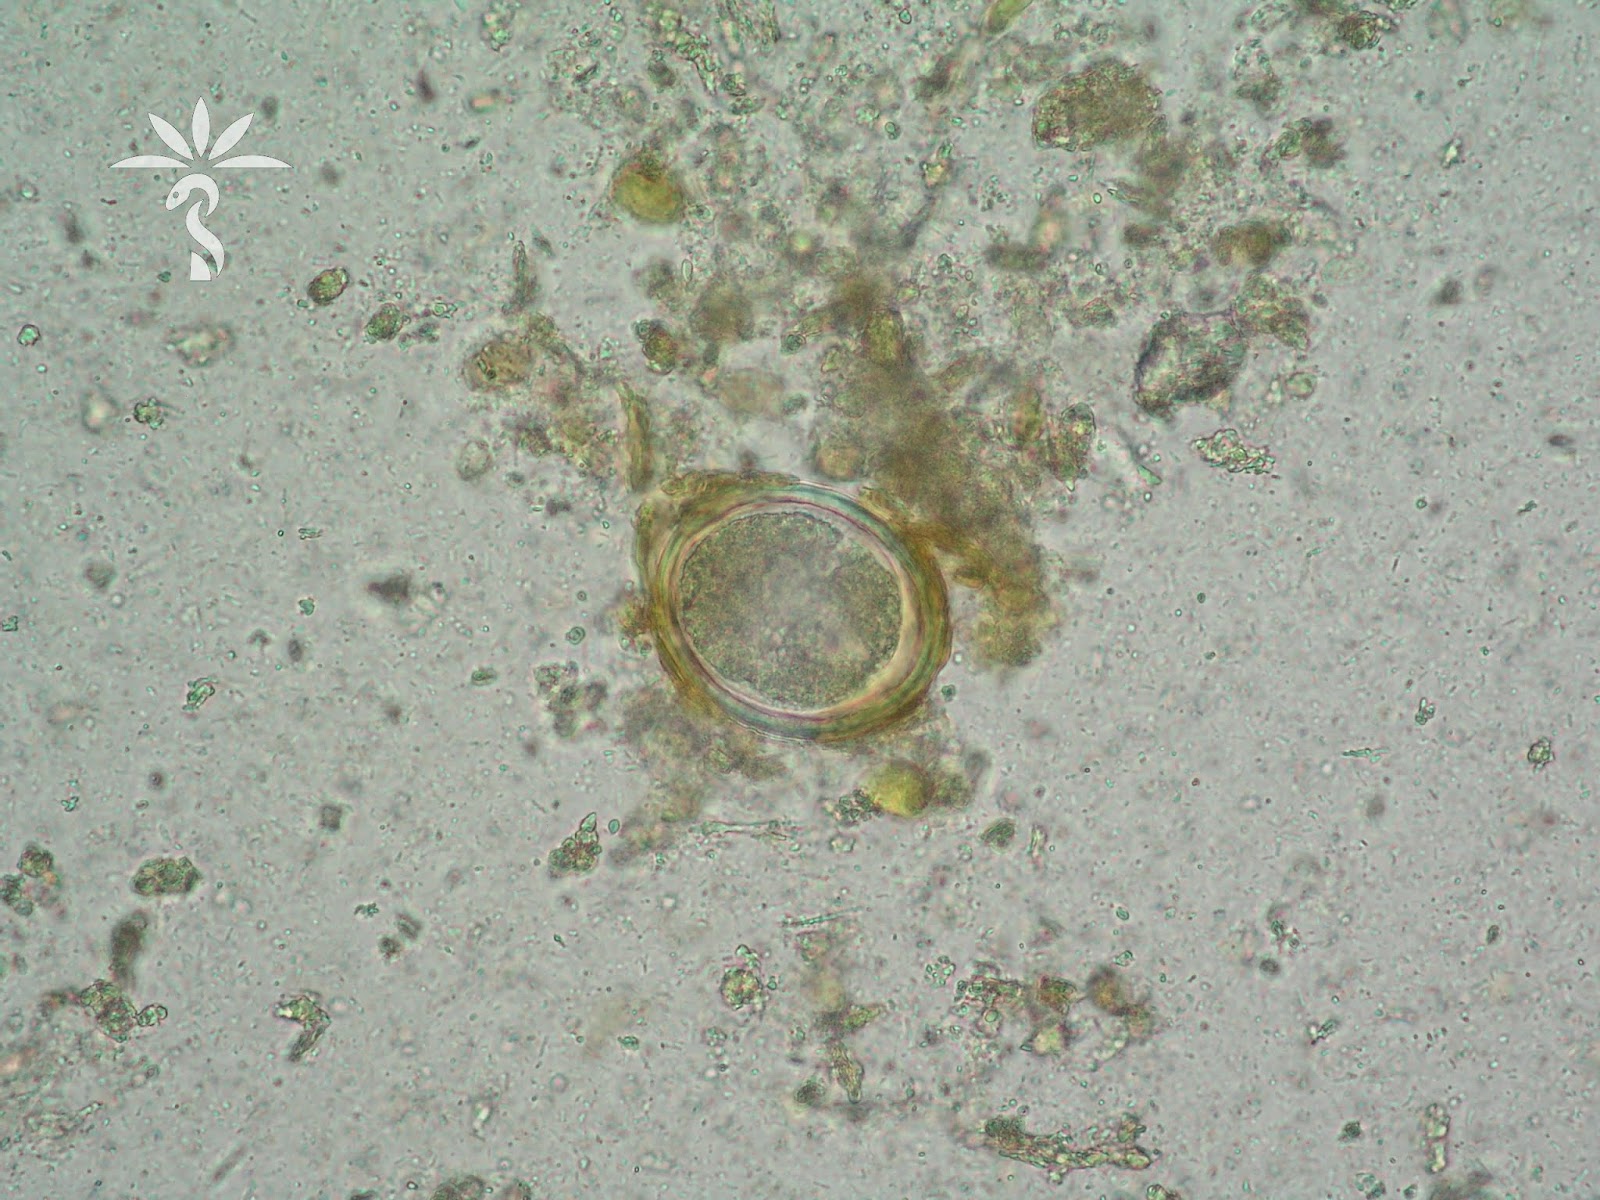

Cdc Dpdx Ascariasis

Ascariasis Image Library Page 3